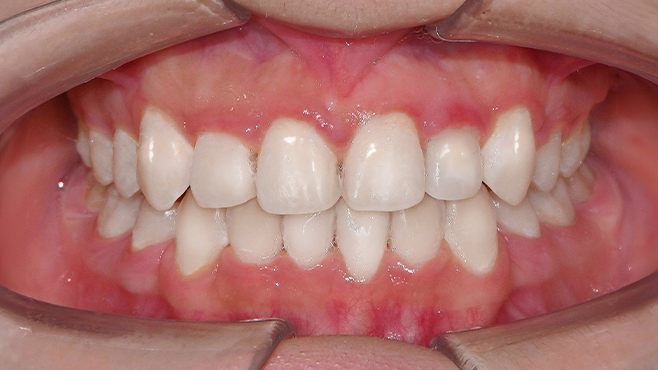

맞는 건 괜찮은데… 충치는 못 참겠습니다|20대 격투기 선수 치과 방문기